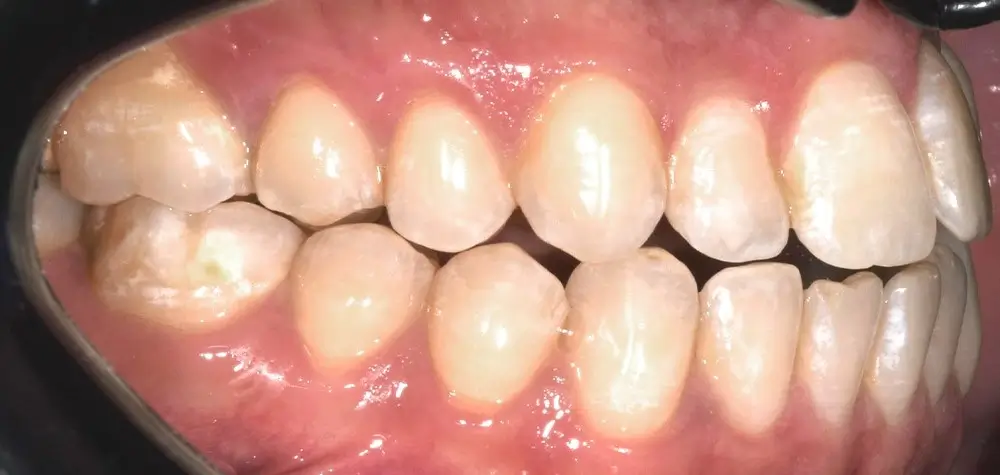

Открытый прикус - Кейс 3

Эффективность устранения дефекта прикуса посредством элайнеров FlexiLigner.

Результаты лечения